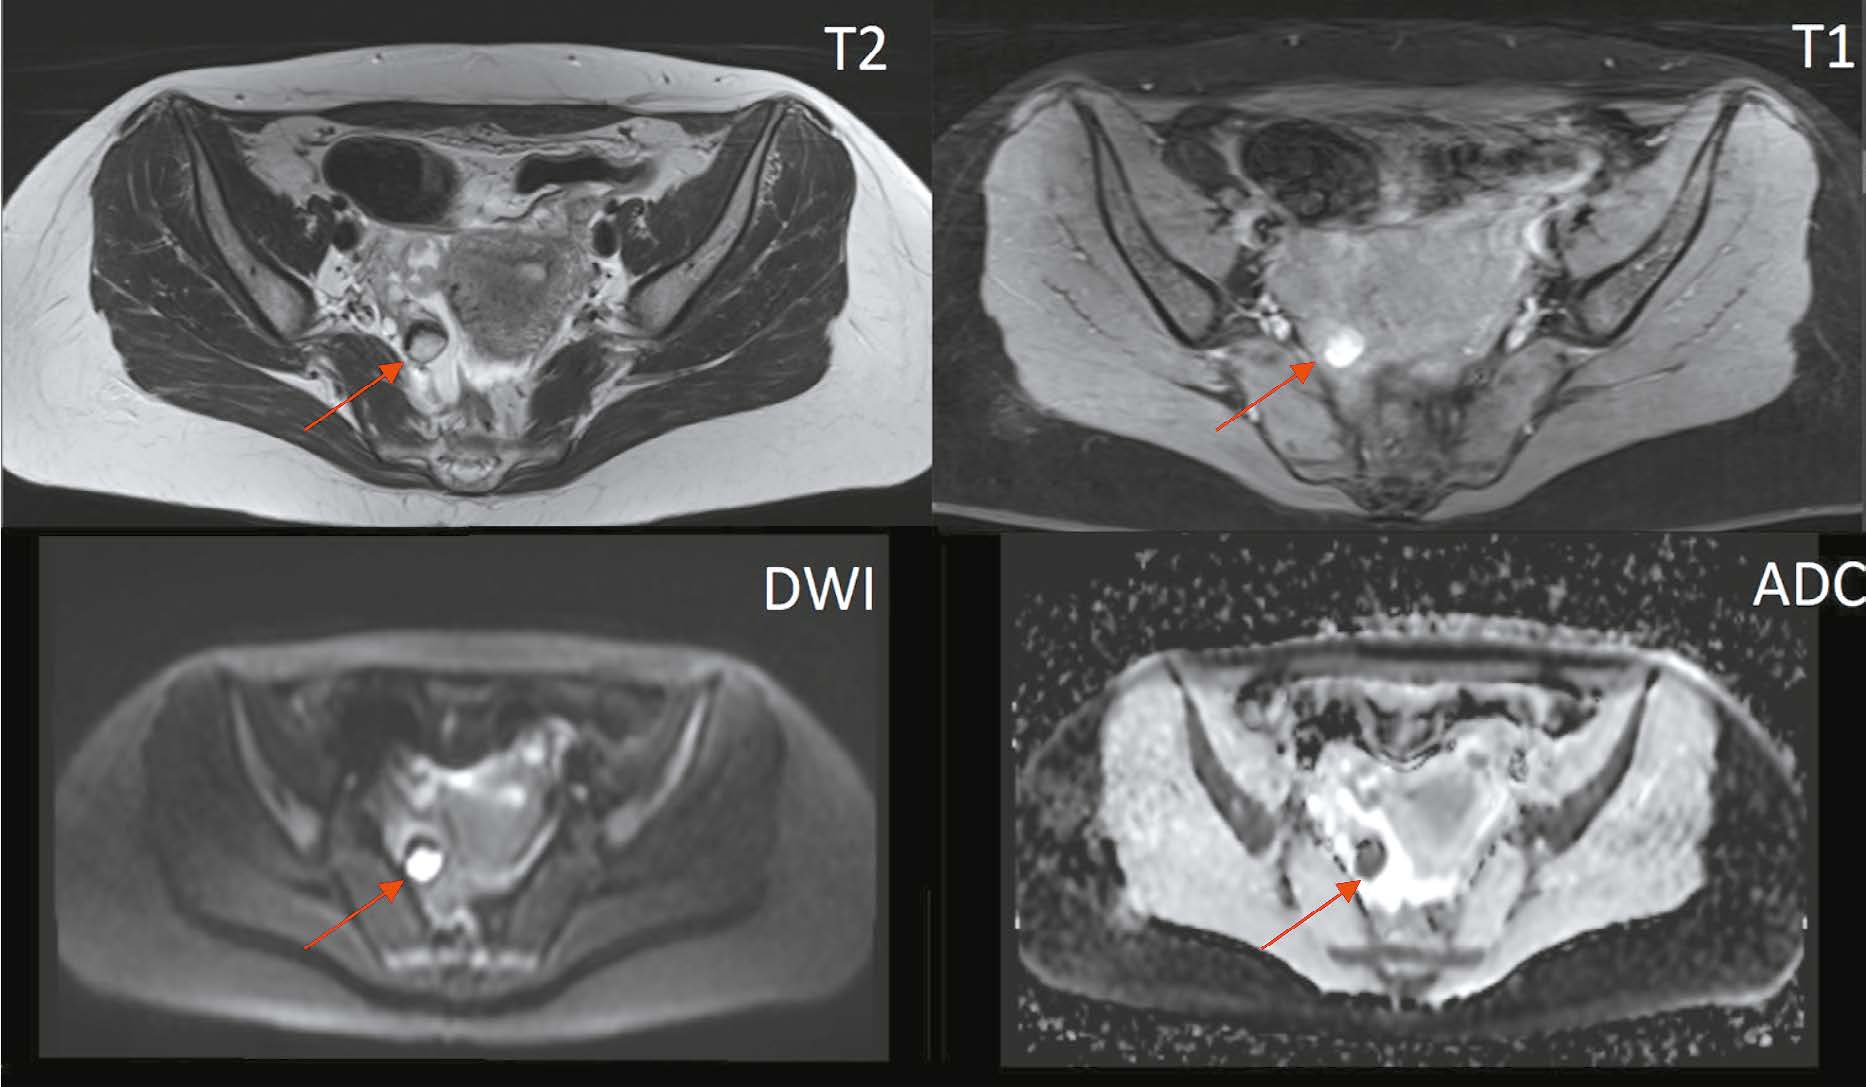

Magnetic resonance imaging in diagnosis of serous adenocarcinoma of fallopian tubes: a case report

Abstract

Serous adenocarcinoma of fallopian tubes is an extremely rare and difficult to diagnose type of cancer of the female reproductive system. This condition is often asymptomatic or has a non specific clinical presentation including serosanguineous vaginal discharge and colic like pain in the lower abdomen and pelvis. These symptoms are reported in the literature as the Latzko’s triad and are considered pathognomonic for tubal cancer, but their combination is observed in less than 15% of patients. The low incidence and lack of the pathognomonic clinical presentation lead to many diagnostic errors or detection of advanced disease, which significantly worsens the patient’s prognosis. An accurate surgical diagnosis is made in only 4% of cases. This case report describes serous adenocarcinoma of fallopian tubes with all signs of the Latzko’s triad and MRI suggestive of serous adenocarcinoma of fallopian tubes at a preoperative stage.

882-892